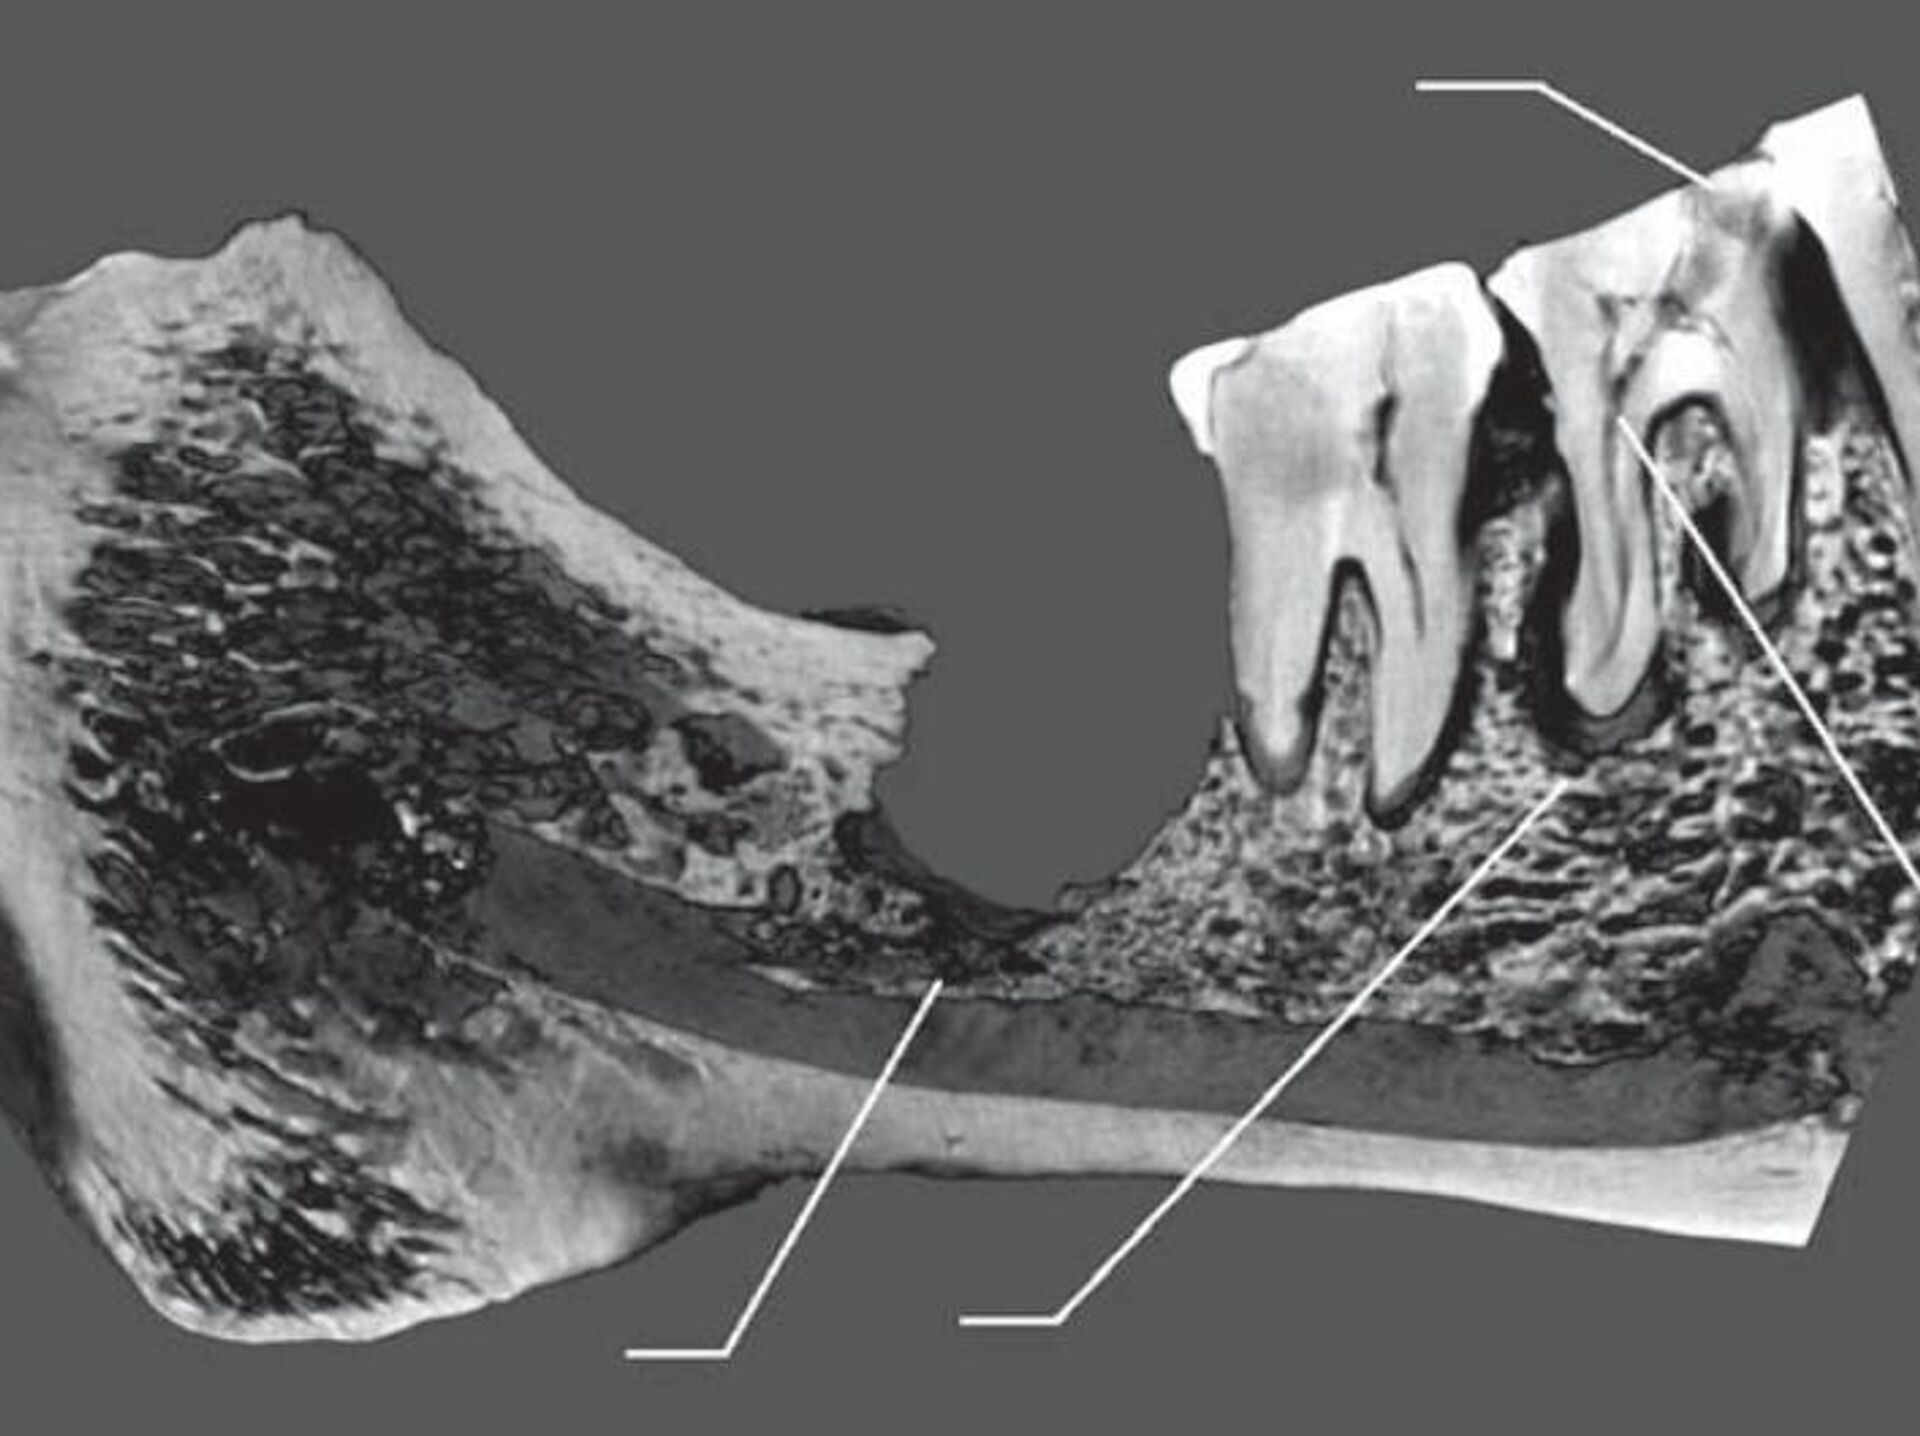

Un grupo explorador del Museo de Antropología y Etnografía de San Petersburgo examinó restos del yacimiento arqueológico Oleneostróvsky, excavado en una isla del norte del lago Onega, en noroeste de Rusia. En una de las tumbas, los científicos encontraron el esqueleto de una mujer adulta de una edad de más de 50 años.Los paleoantropólogos prestaron atención al cráneo de esta persona porque observaron en él indicios de intervenciones quirúrgicas. En opinión de los autores, esta operación era necesaria porque la caries había provocado el desarrollo de una pulpitis crónica y, posteriormente, de una periodontitis apical y una osteomielitis. Además, los científicos descubrieron que esta mujer también se fracturó el primer molar del otro lado de la mandíbula cuando, "al parecer, mordió algún objeto duro". Como resultado, el diente se partió en tres trozos, dos de los cuales le fueron extraídos en distintos momentos. En el alvéolo de este molar, los investigadores registraron una incisión que se hizo para extraer una parte del diente o con otros fines terapéuticos. Sin embargo, la mujer murió poco después de esta operación. De acuerdo con el artículo, probablemente, se desarrolló una inflamación purulenta aguda pocos días después de la intervención, tras la cual la mujer murió de septicemia.De esta forma, se trata del caso más antiguo conocido de intervención dental hallado en el norte de Eurasia.

Un grupo explorador del Museo de Antropología y Etnografía de San Petersburgo examinó restos del yacimiento arqueológico Oleneostróvsky, excavado en una isla del norte del lago Onega, en noroeste de Rusia. En una de las tumbas, los científicos encontraron el esqueleto de una mujer adulta de una edad de más de 50 años.

Los paleoantropólogos prestaron atención al cráneo de esta persona porque observaron en él indicios de intervenciones quirúrgicas.

"A la mujer se le cortó el tercer molar junto con un trozo de la mandíbula inferior, y que la operación fue un éxito, por lo que la paciente permaneció con vida al menos varios meses", destaca el artículo publicado en la revista Arqueología, Etnología y Antropología de Eurasia.

En opinión de los autores, esta operación era necesaria porque la caries había provocado el desarrollo de una pulpitis crónica y, posteriormente, de una periodontitis apical y una osteomielitis.

Además, los científicos descubrieron que esta mujer también se fracturó el primer molar del otro lado de la mandíbula cuando, "al parecer, mordió algún objeto duro". Como resultado, el diente se partió en tres trozos, dos de los cuales le fueron extraídos en distintos momentos.

En el alvéolo de este molar, los investigadores registraron una incisión que se hizo para extraer una parte del diente o con otros fines terapéuticos. Sin embargo, la mujer murió poco después de esta operación. De acuerdo con el artículo, probablemente, se desarrolló una inflamación purulenta aguda pocos días después de la intervención, tras la cual la mujer murió de septicemia.

De esta forma, se trata del caso más antiguo conocido de intervención dental hallado en el norte de Eurasia.